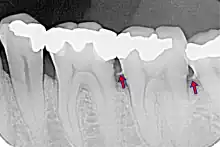

El cálculo dental, también denominado sarro, odontolito, piedra y tártaro dental, es la acumulación de sales de calcio y de fósforo sobre la superficie dental[1]. Se trata del resultado de la mineralización de la placa bacteriana, esto es, del conjunto de microorganismos, saliva y restos alimenticios que se van depositando sobre las piezas dentales.

Según su localización, se distingue entre el sarro supragingival (amarillo), cuando se halla por encima de la línea de la encía, y el infragingival o subgingival (marrón), cuando se sitúa por debajo de esa línea.